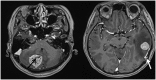

Perivascular epithelioid cell tumour is a rare mesenchymal tumour with distinct immunohistochemical profile. While it is known to occur in various anatomical sites, the central nervous system had always been a protected site for primary or secondary perivascular epithelioid cell tumours. We describe a 61-year-old lady who presented with symptoms of raised intracranial pressure, 3 months after the resection of duodenal and thoracic tumours which were histologically consistent with perivascular epithelioid cell tumour. She was investigated and then subsequently subjected to resection of two metastatic intracranial lesions. The radiological, intraoperative as well as histopathological findings of the metastatic lesions are discussed. Metastatic perivascular epithelioid cell tumour of the brain is extremely rare. However, patients who are stratified as high risk for recurrence or metastases should undergo an early magnetic resonance imaging/computed tomography of the brain in addition to a whole-body positron emission tomography scan, to allow for early detection and management of these tumours.